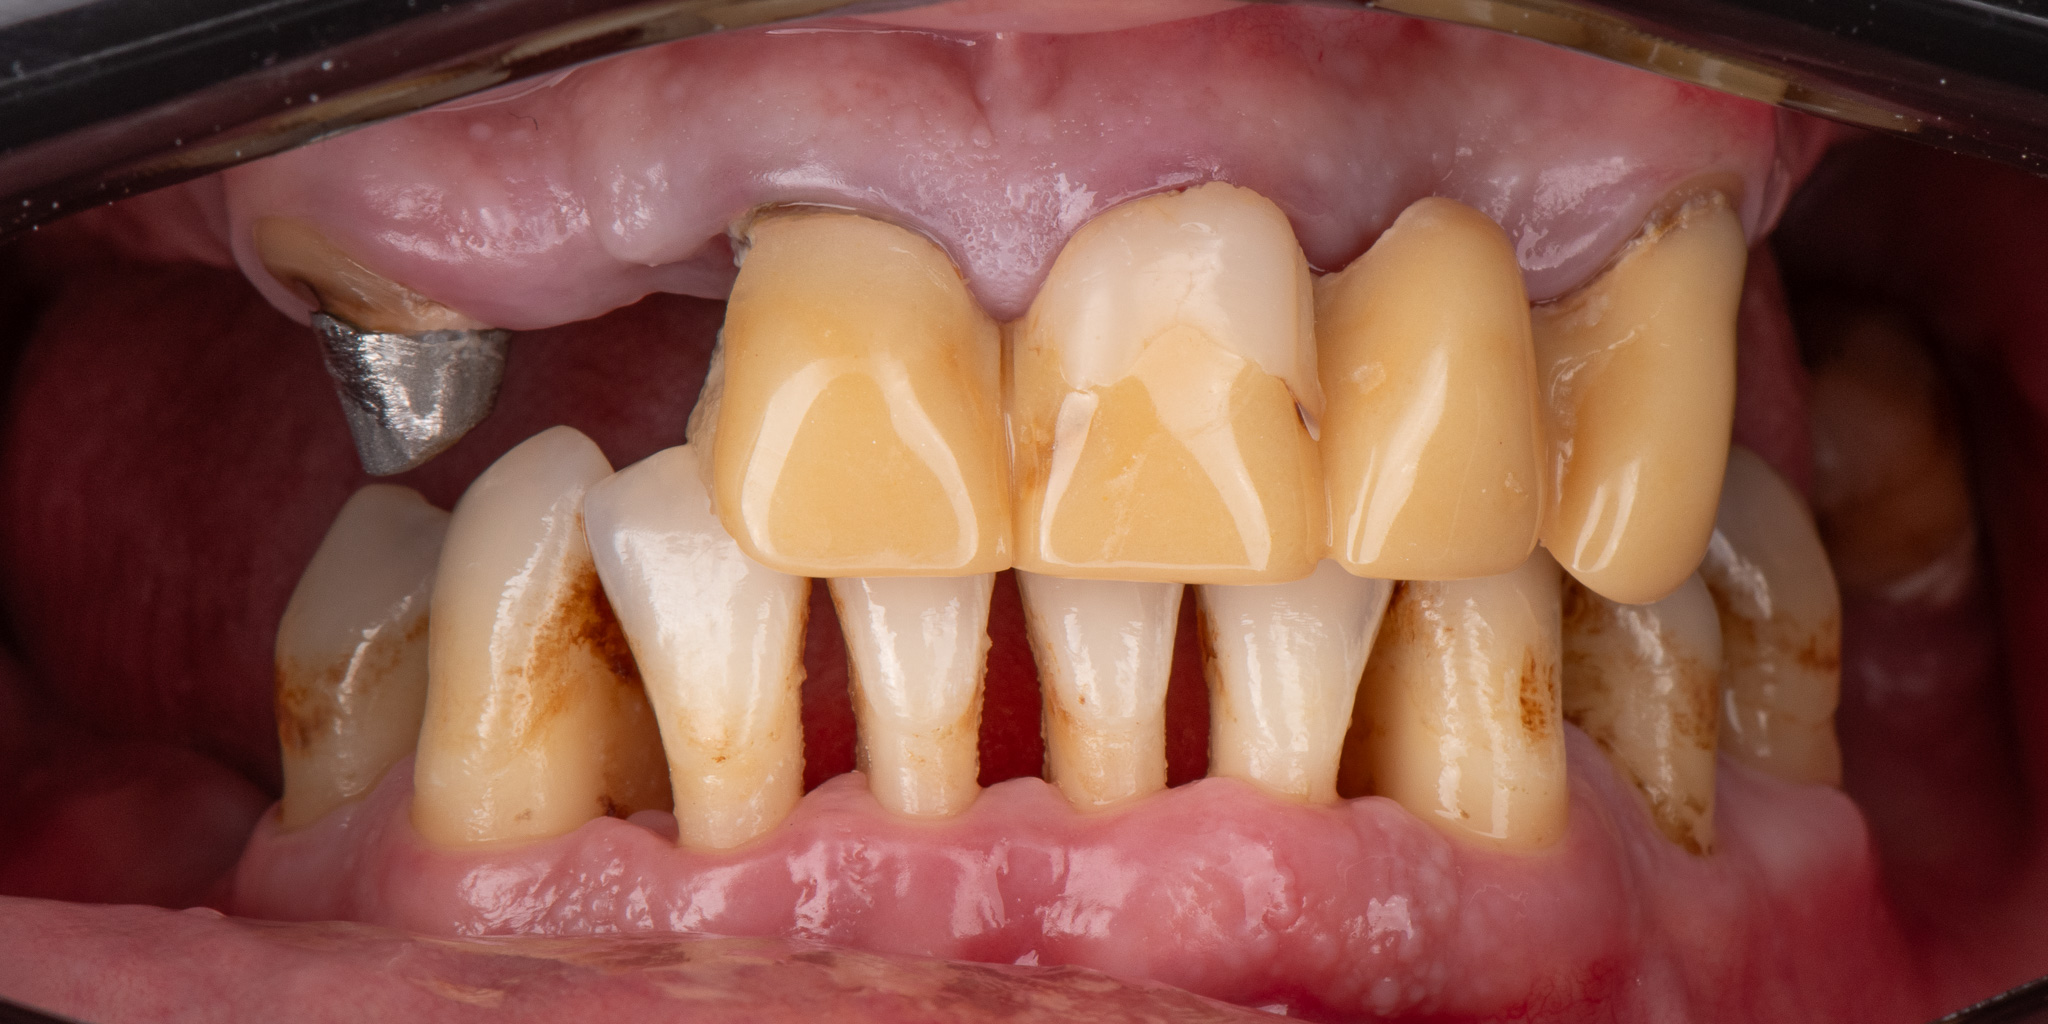

Pacjent 3

Pacjent zgłosił się ze zużytym tymczasowym mostem protetycznym

Zaplanowane leczenie obejmowało wykonanie nowych koron ceramicznych na podbudowie metalowej oraz protez szkieletowych górnej i dolnej.